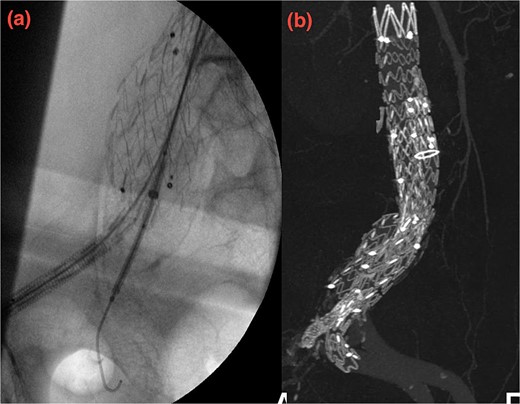

Despite these interventions, the patient experienced further episodes of acute limb ischemia (Fig. 4), leading to thrombolytic therapy a month later. This recurrence prompted a reevaluation of the treatment strategy. We considered extending the graft limb, which would involve sacrificing the hypogastric artery, or using an iliac artery extension with an iliac side branch. We ultimately chose the latter and implanted an E-iliac stent graft (Jotec ISB system) (Fig. 5a and b). Preservation of the hypogastric artery was prioritized, although extending into the external iliac artery would have been a viable alternative. However, the multidisciplinary team decided the preservation of the hypogastric artery would be more appropriate in this patient. The patient was discharged without anticoagulants.

(a, b) Intraoperative images showing implantation of the iliac side branch device ISB.

We believed the atheroma distal to the flared limb was the source of acute ischemia and subsequent embolization events. After 1 year of follow-up, the patient showed sustained improvement. Our treatment strategy focused on preserving the internal iliac artery while excluding disease in the common iliac artery using the iliac side branch system.